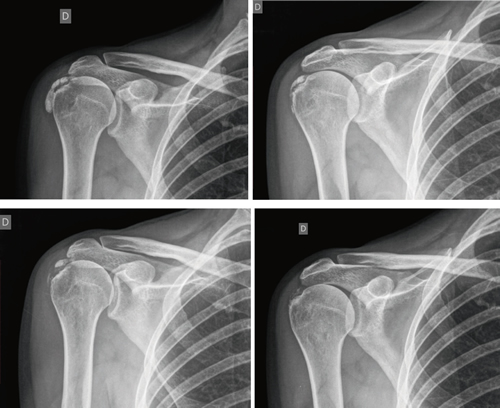

The average number of sessions in our series was 20. The criteria for continuing or stopping treatment was the radiological and clinical evolution (Figures 4 and 5). The interventions were performed up to a maximum of 40 sessions. Perrón treated patients for 9 sessions (3 weekly sessions for 3 weeks) (14). Leduc treated with 10 sessions (3 per week for the first two weeks; then one weekly for 4 weeks) (15). Rioja-Toro treated patients for 40 sessions (5 times per week) and evaluated them at 20 and 40 sessions (3). Chico-Álvarez treated patients between 15 and 30 sessions depending on the radiological evolution (5 times per week) (1).

Fig. 4. 47-year-old female patient with formative right supraspinatus calcific tendinitis who, after 30 sessions of iontophoresis, decreased pain measured by VAS from 6/10 to 3/10 and calcification from 38 mm to 8 mm (assessments at onse and at 10, 20 and 30 sessions, respectively).